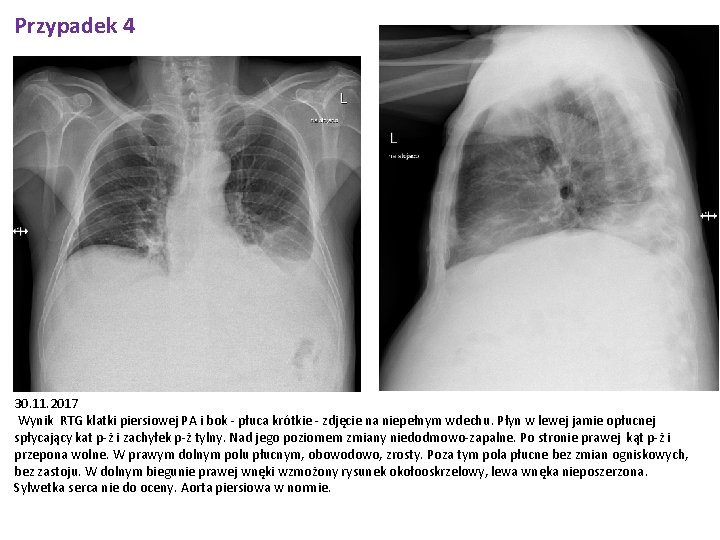

Przypadek 4 „Kasztanowy ludzik” Pacjent 59 letni, dotychczas na nic przewlekle się nie leczący został przyjęty do Kliniki w związku z zażółceniem twardówek oraz powłok skórnych, narastającym obwodem brzucha. Podaje ponadto utratę masy ciała ok 10 -15 kg w ciągu ostatnich 3 -4 miesięcy. AST 84, ALT 22 bilirubina 69, 2 umol/l (4, 05 mg/dl) GGTP 1190, ALP 694 (5 xggn) niedokrwistość normocytarna krzepnięcie w normie W USG jamy brzusznej: Masywna ilość płynu w jamie otrzewnej, grubości: okołowątrobowo -wzdłuż lewego płata 38 mm -wzdłuż prawego płata 45 mm; na prawej flance do 70 mm; na lewej flance do 73 mm; okołosledzionowo do 24 mm; międzypętlowo do 134 mm. Wątroba niejednorona, o nierównych obrysach, z cechami drobnoguzkowej przebudowy - cechy marskości, bez wyodrębniających się zmian ogniskowych. Drogi żółciowe wewnątrz- i zewnątrz-wątrobowe nieposzerzone, bez cech kamicy. Pęcherzyk żółciowy niepowiększony, o pogrubiałej ścianie (jak przy obecności płynu), bez uchwytnych cech kamicy.

Przypadek 4 30. 11. 2017 Wynik RTG klatki piersiowej PA i bok - płuca krótkie - zdjęcie na niepełnym wdechu. Płyn w lewej jamie opłucnej spłycający kat p-ż i zachyłek p-ż tylny. Nad jego poziomem zmiany niedodmowo-zapalne. Po stronie prawej kąt p-ż i przepona wolne. W prawym dolnym polu płucnym, obowodowo, zrosty. Poza tym pola płucne bez zmian ogniskowych, bez zastoju. W dolnym biegunie prawej wnęki wzmożony rysunek okołooskrzelowy, lewa wnęka nieposzerzona. Sylwetka serca nie do oceny. Aorta piersiowa w normie.

Przypadek 4 Epikryza Pacjent l. 59 bez chorób przewlekłych w wywiadzie został przyjęty z powodu zażółcenia powłok skórnych i twardówek, powiększenia obwodu brzucha oraz utraty masy ciała ok. 10 kg w ciągu 3 miesięcy. Pacjent podaje nadużywanie alkoholu. Przyjęty w stanie ogólnym średnim, przytomny, w pełnym kontakcie słowno-logicznym, skóra i twardówki nieznacznie zażółcone, wydolny krążeniowo i oddechowo, brzuch wysklepiony powyżej poziomu klatki piersiowej, bez objawów otrzewnowych, bez obrzęków obwodowych. W badaniach laboratoryjnych cechy toksycznego uszkodzenia wątroby, podwyższone parametry zapalne, wykluczono zakażenie wirusami HBV, HCV. W USG jamy brzusznej wątroba niejednorododna, o nierównych zarysach, z cechami przebudowy drobnoguzkowej. Włączono leczenie moczopędne, empiryczną antybiotykoterapię, dwukrotnie wykonano paracentezę (płyn puchlinowy bez cech zapalenia, posiew płynu ujemny, komórek atypowych nie stwierdzono). Po uzyskaniu poprawy stanu ogólnego pacjenta wypisano do domu w stanie ogólnym dobrym.